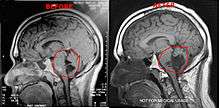

Magnetic resonance imaging (MRI) and computed tomography (CT) brain scans can be used to identify these tumors.

It has been seen that a few patients have tumors that grow unusually fast, especially after surgery. After surgery it is highly suggested the patients get quarterly MRI's to monitor their tumors or as per neurosurgeons/neurologists order. If monitoring the tumor, it is suggested to use the same facility for each scan. Using different facilities can result in minor variations in the scan which can result in false measurements of the brain tumor.